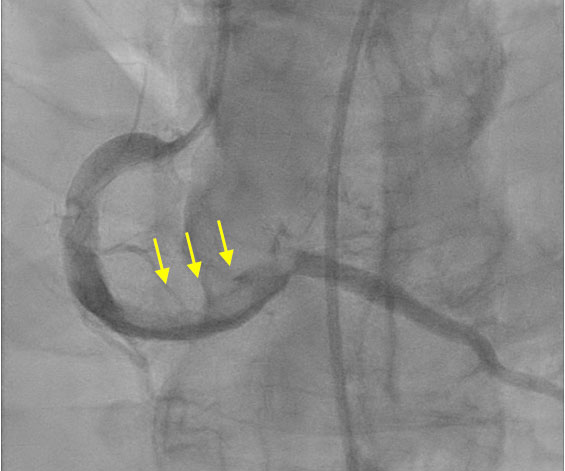

Code STEMI was activated. The patient received 324 mg of aspirin, 80 mg of atorvastatin, one nitroglycerin tablet, and an intravenous heparin drip prior to being transferred for emergent cardiac catheterization. Coronary angiography demonstrated diffuse, severe coronary artery ectasia (Figure 2) with complete (100%) thrombotic occlusion of the distal RCA and a large thrombus burden at the mid-RCA segment (Figure 2). PCI was performed with the placement of a drug-eluting stent in the distal RCA, resulting in the restoration of TIMI III flow to the right posterior descending artery. However, a residual thrombus remained in the mid-to-distal RCA, and occlusion of the right posterior ventricular branch persisted (Figure 3).

Figure 2

Figure 2 Left: Anterior oblique-caudal view demonstrating diffuse coronary ectasia involving the left anterior descending (LAD) and left circumflex (LCX) arteries, without significant obstructive lesions. Right: Severe dilation of the right coronary artery (RCA) with distal branch obstruction (yellow arrow).